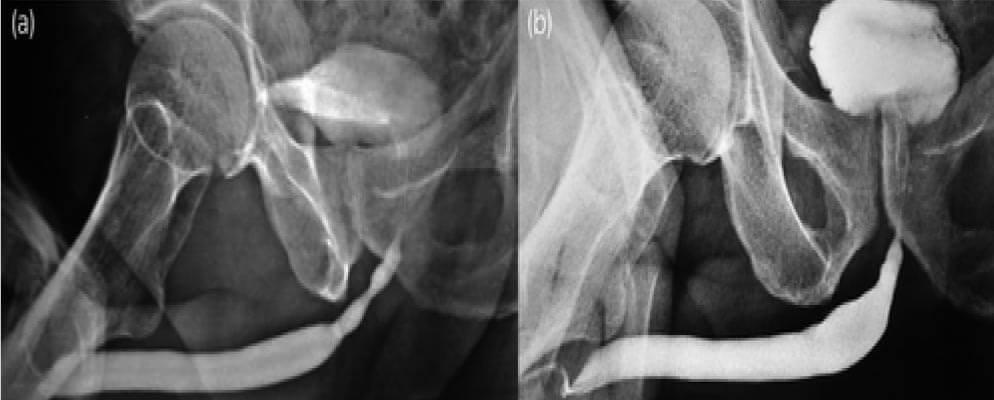

Figure 4: (a)(b) Pre-Post-BEES-HAUS procedure Urethrogram

The urethral catheter was removed after 3 weeks. Follow up was carried out every 6 months by symptom assessment and uroflowmetry. A check Urethroscopy was carried out at 6 months. Urethrogram was carried out at 1 year follow up.

After urethral catheter removal, all patients voided well with a good stream. There was a symptomatic improvement in all patients, and uroflow improved with a mean flow of 24 mL/s. The check Urethroscopy carried out at 6 months, 1 year and after 2 years are shown in Fig 2,3,4. Four patients were voiding well and did not require any auxiliary procedure at 3 years of follow up. Recurrence was seen in two patients at 18 months in one patient and at 2 years in the other.